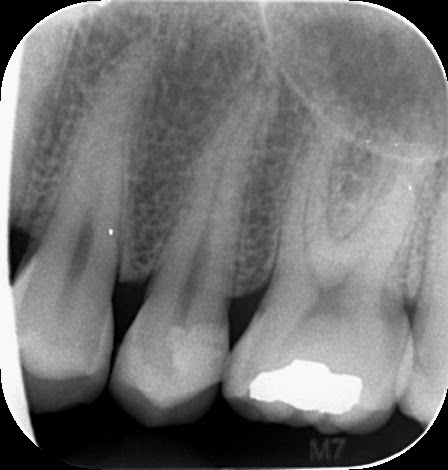

X ray of tooth that needs root canal. One of the most valuable aids that a dentist has in diagnosing a tooths need for root canal therapy is x-ray examination. In fact it seems unlikely that any evaluation of a suspect tooth wouldnt need to include at least some probably two or more conventional radiographs traditional 2-dimensional x-ray pictures. There is no indication of inflammation near the root tip which is the first indication of an infected tooth that can be seen on an x-ray.

And you are saying that the tooth feels fine. Finally there is some clear evidence on the x-ray that the root of the tooth is healthy. If you look at a clearly healthy tooth for example the canine tooth next to this one.

If it tooth has a radiographic area on the x-ray that can be visualized by the dentist this indicates it will need a root canalA new three dimensional x-ray which your dentist may be doing called a CBCT will better be able to see a change around the root of the tooth. Does an X-ray always show whether a tooth needs a root canal or not. Although radiographs often do show a widening of the ligament at the apex when an endodontic infection is present not all teeth that require root canal treatment do show this tell tale sign.

Also a dead tooth frequently gets discolored withor without Invisalign but only time will tell if that will be a fate for your tooth. I have a similar case and we decided to wait with the patient and just monitor the tooth rather than jumping to do. On the before x-ray you can see the condition of the tooth when the patient presented to the office.

The reason for needing a root canal is often a recurrent decay that is too close to the nerve andor the infection at the root of the tooth called apex the darker area surrounding the root as seen on the before x-ray. A CBCT is a 3-dimensional X-ray that allows the endodontist to look at the tooth in all planes to help diagnose a pattern of bone loss that may be indicative of a vertical fracture canal anatomy that may not have been addressed in the original endodontic therapy and other factors that will help your endodontist determine the best treatment. In fact its early acute phase periapical periodontitis a tooth can look perfectly fine on an X-ray but tap on that tooth with a mirror handle and the patient may well want to throttle you.